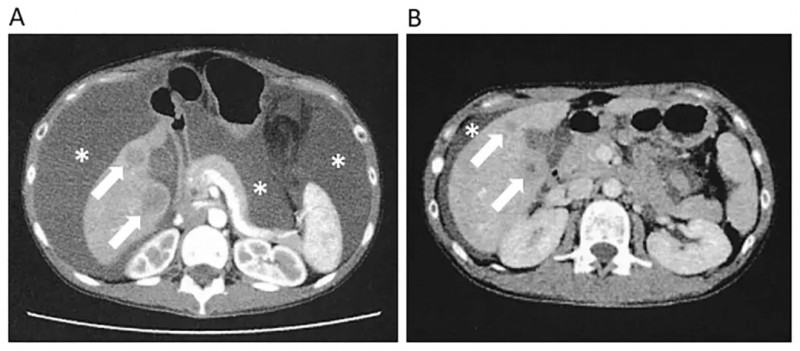

2、腹水显著减少,腹膜播散获抑制:NK细胞治疗前,患者腹部CT清晰显示大量腹水(详见下图A);治疗期间腹水减少趋势明显,第56天复查腹部CT时,腹水较确诊时大幅减少,同时肝转移灶也有所缩小(详见下图B)。这一变化充分证实,NK细胞疗法在抑制腹膜播散方面发挥了积极作用。

▲图源“Cureus”,版权归原作者所有,如无意中侵犯了知识产权,请联系我们删除